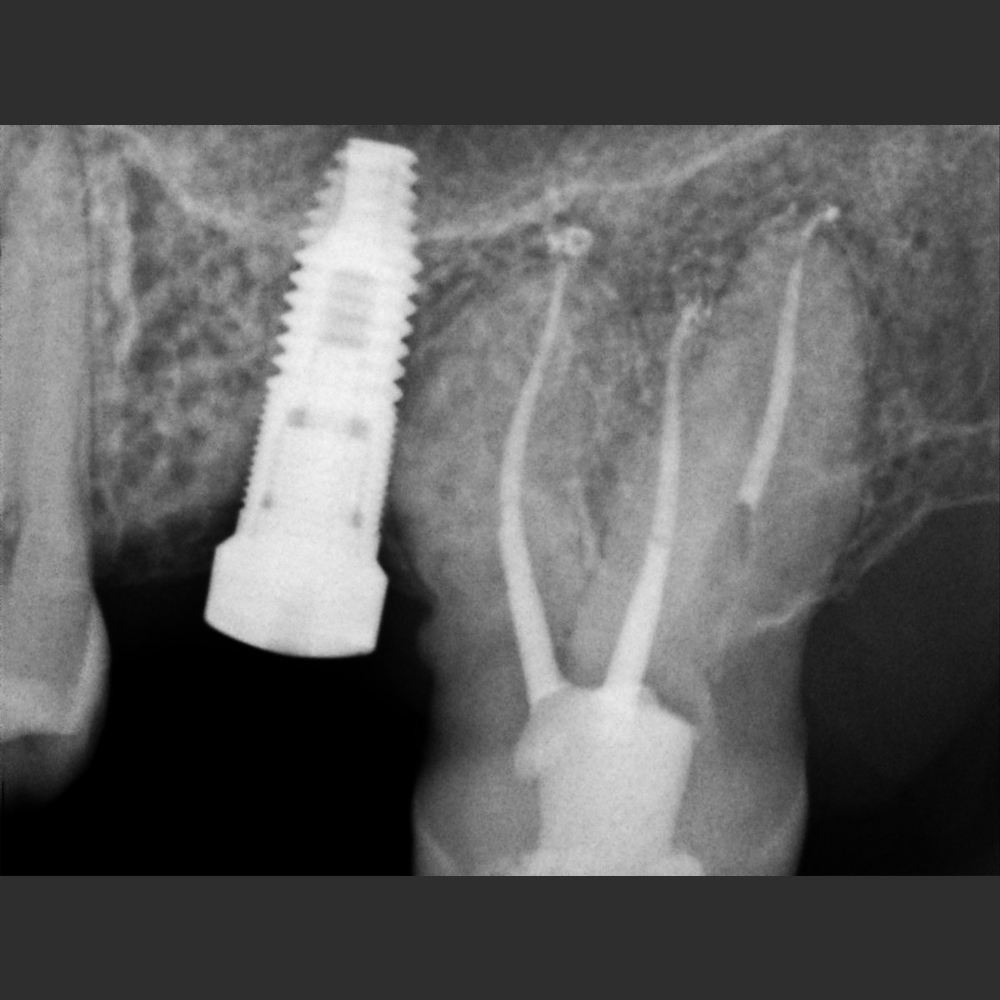

New IDA –– Tamaño 1 (área activa: 20x30 mm)

New IDA son los sensores intraorales de la linea New Ida con soluciones eficientes de las imágenes para un diagnóstico nítido, preciso y seguro.

Captura imágenes de alta definición en tiempo real.